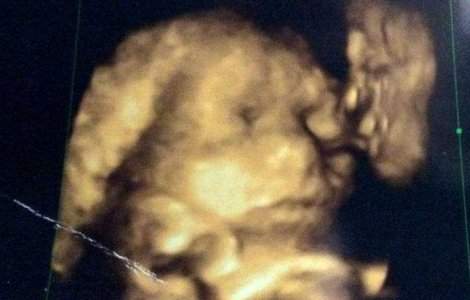

Fantoma bunicului a aparut in ecografia copilului nenascut.